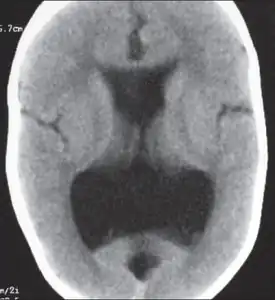

Colpocephaly is a cephalic disorder involving the disproportionate enlargement of the occipital horns of the lateral ventricles and is usually diagnosed early after birth due to seizures. It is a nonspecific finding and is associated with multiple neurological syndromes, including agenesis of the corpus callosum, Chiari malformation, lissencephaly, and microcephaly.[1] Although the exact cause of colpocephaly is not known yet, it is commonly believed to occur as a result of neuronal migration disorders during early brain development, intrauterine disturbances, perinatal injuries, and other central nervous system disorders.[2] Individuals with colpocephaly have various degrees of motor disabilities, visual defects, spasticity, and moderate to severe intellectual disability.[3] No specific treatment for colpocephaly exists, but patients may undergo certain treatments to improve their motor function or intellectual disability.

Colpocephaly is characterized by disproportionately large occipital horns of the lateral ventricles (also frontal and temporal ventricles in some cases). MRI and CT scans of patients demonstrate abnormally thick gray matter with thin poorly myelinated white matter. This happens as a result of partial or complete absence of the corpus callosum. Corpus callosum is the band of white matter connecting the two cerebral hemispheres. The corpus callosum plays an extremely important role in interhemispheric communication, thus lack of or absence of these neural fibers results in a number of disabilities.[12]

The lemon sign on CT scans of patients refers to the shape of the fetal skull when the frontal bones lose their normal convex contour and appear flattened or inwardly scalloped. This gives the skull a shape similar to that of a lemon. The sign is seen on transverse sonograms of the fetal cranium obtained at the level of the ventricles. A special case is found in literature where lissencephaly, colpocephaly, and septal agenesis are all present together. The CT scans of the patient shows the ventricular system having a unique appearance of a crown of a king. This is referred to as the 'CROWN SIGN'.[8]

After birth, MR imaging can be done to look for cephalic abnormalities. This is the most commonly used method for diagnosing colpocephaly. Physicians look for abnormally large occipital horns of the lateral ventricles and diminished thickness of white matter.[12] Spinal tapping is not a preferred method for diagnosis because newborn babies with colpocephaly or hydrocephaly have open fontanelles which makes it difficult to collect CSF. Also, colpocephaly is not associated with increased pressure.[13]